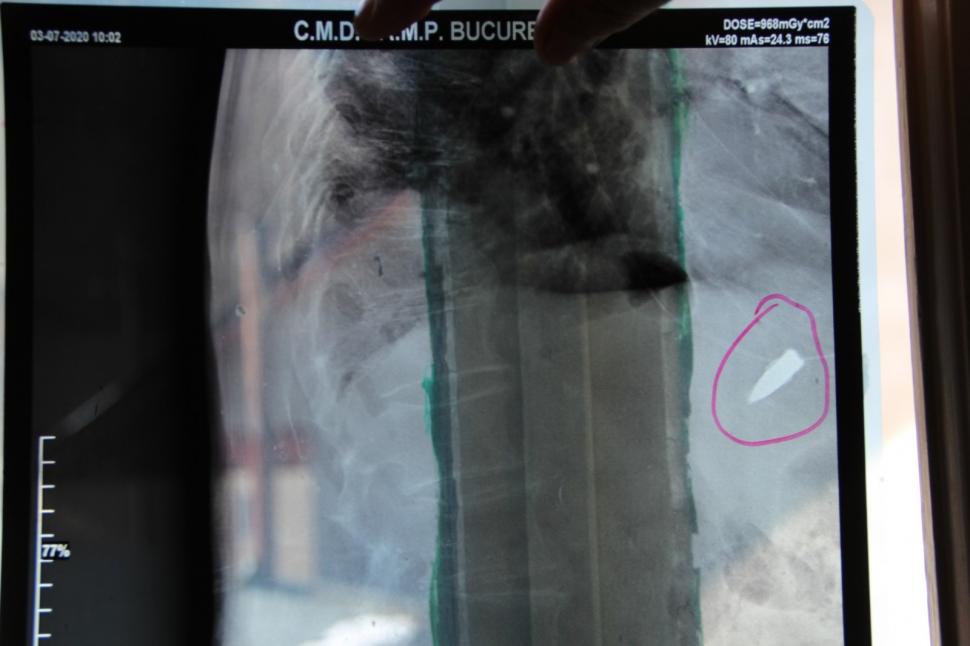

Veteranul de război care trăiește de 8 decenii cu un glonț lângă inimă. "Am stat peste o lună în spital, iar, ulterior, comisia de evaluare a decis să revin pe front"